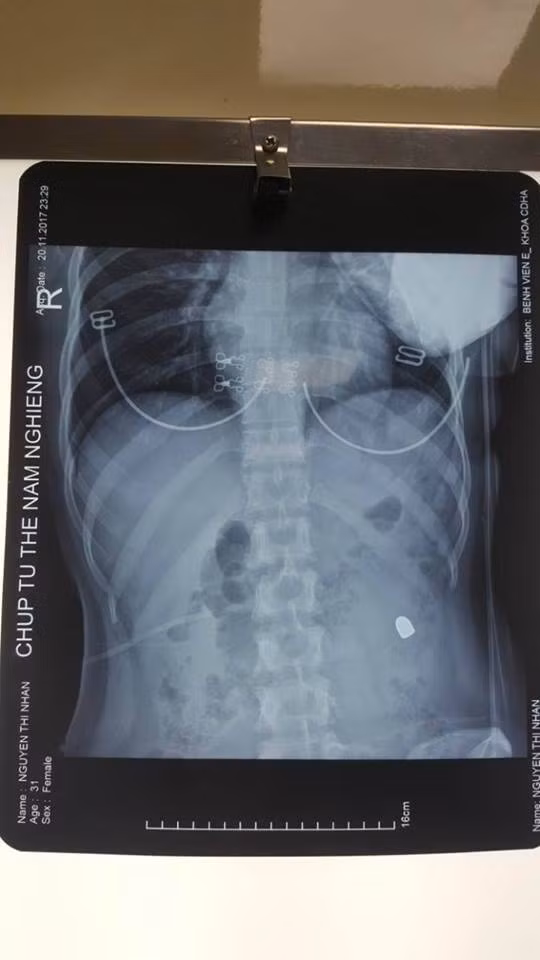

| Nữ bệnh nhân bị đạn bắn vào bụng. |

| Các bác sĩ mổ lấy đầu đạn ra khỏi bụng bệnh nhân. |